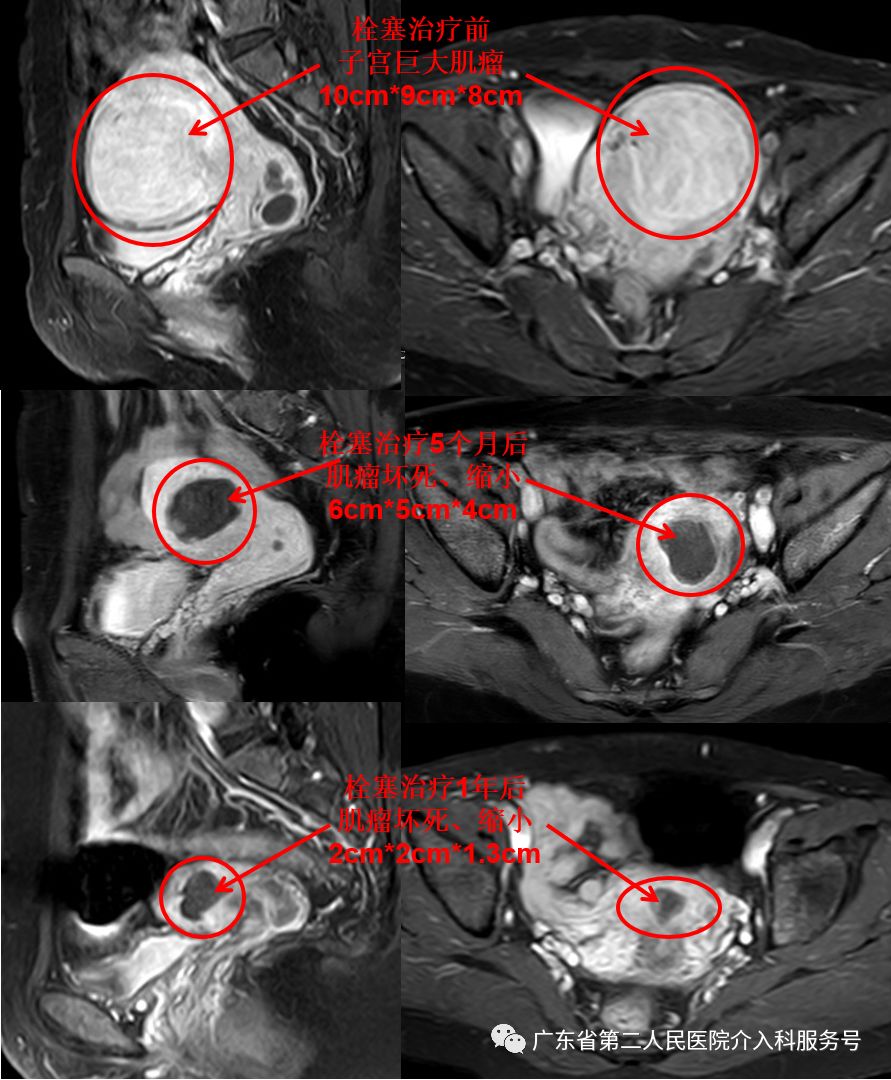

下图为梁女士的磁共振检查:子宫巨大肌瘤(国际妇产科联盟(FIGO)子宫肌瘤Ⅴ型,大小约10m*9cm*8cm)

治疗后差不多1个月,梁女士的“大姨妈”驾到,量正常,第7天即干净,再也没有淋沥不净的尴尬。3个月后,梁女士例假依然正常,已没有贫血貌,现在久坐后站立时再也没有出现眼前发黑(黑蒙)的现象。梁女士高兴的说:终于摆脱“大姨妈”来时排山倒海,大量血块,淋沥不净的烦恼,关键是可以和其他女性一样保留子宫,正常来月经,没有血块,不会淋沥不净,生活也舒坦了。门诊复查血红蛋白在正常范围,磁共振如下(子宫肌瘤已坏死、吸收、缩小(6cm*5cm*4cm),随后坏死的肌瘤还会继续吸收、缩小)。

1年后,梁女士例假依然正常,没有贫血。复查的磁共振如下(子宫肌瘤已坏死、吸收、缩小(2cm*2cm*1.3cm))。

针眼妙方(子宫动脉栓塞)治疗后,坏死的子宫肌瘤逐渐吸收、缩小……让来无影的子宫肌瘤去无踪